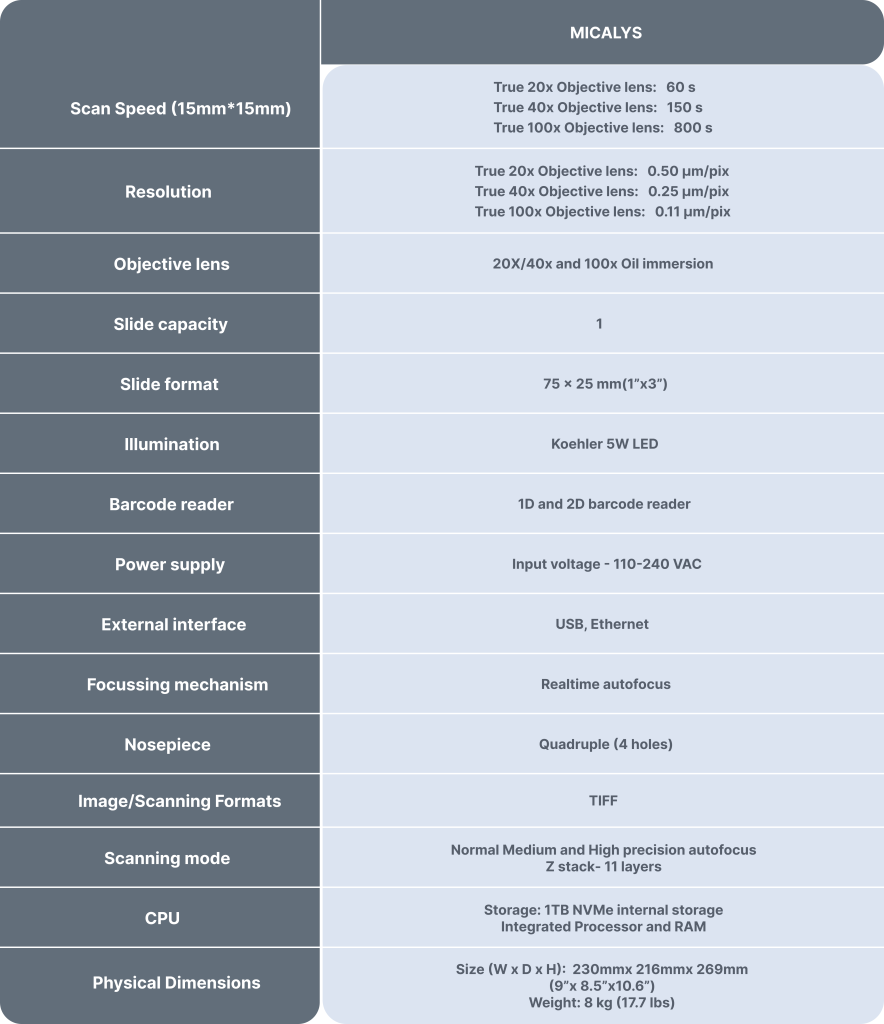

Technical Specifications